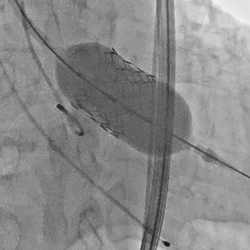

术前经详尽影像学重建、评估及病例讨论,计划经右侧股动脉植入25#球扩式介入瓣。术中使用21#球囊进行预扩,植入25# Renatus®介入主动脉瓣。手术全程顺利,血流动力学稳定,主动脉瓣植入位置理想,功能表现出色,DSA及TEE评估无瓣中反流,仅有轻微瓣周反流。主动脉瓣峰值流速由术前4.4m/s降至1.6m/s,平均压差由术前49mmHg降至4.4mmHg。

球扩释放瓣膜 术后主动脉根部造影